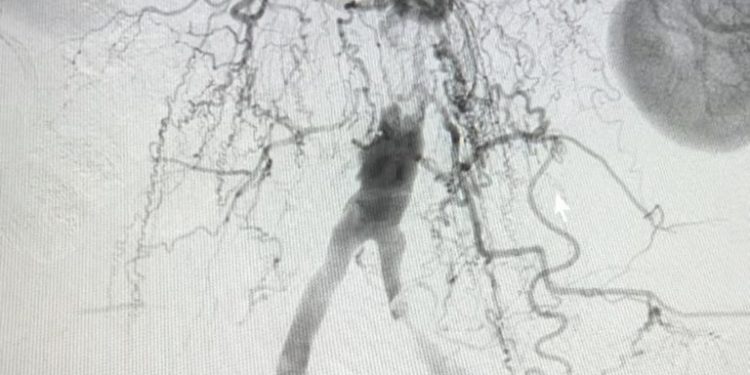

A cirurgia para sanar o problema foi realizada com sucesso, por meio da utilização de técnicas vasculares. Foi feita uma angioplastia com implantação de um stent revestido. Mesmo sendo um procedimento de alta complexidade, foi executado sem nenhum corte e de forma minimamente invasiva devido às técnicas avançadas que foram utilizadas.

De acordo com o cirurgião vascular e endovascular Willamax Oliveira, responsável pelo procedimento, a angioplastia (com implantação de stent) foi crucial para a vida da paciente. “Ela chegou aqui com dores ao realizar pequenas caminhadas, o que a impossibilitava de realizar atividades do cotidiano, de rotina. Ela estava sem condições de fazer as coisas básicas e trazendo complicações graves para ela”, contou o cirurgião.